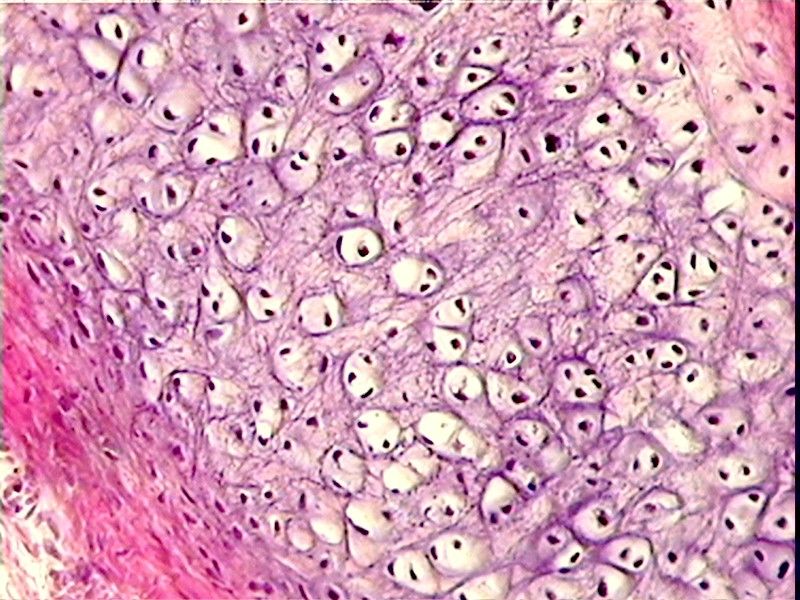

2. Hyaline cartilage

1. Found in ends of bones at joints.